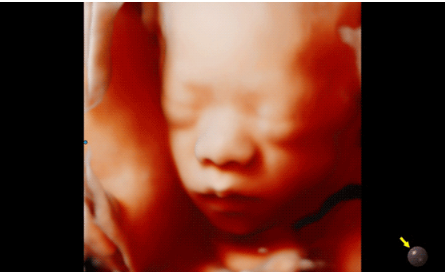

近日三星醫(yī)療推出了一款全新的母嬰超聲系統(tǒng)——Hera i 10。該款產(chǎn)品除了成像能力本身,人性化的座椅設計,探頭擺放位置等也是亮點之一。

Hera i 10繼承并升級了全球首款5D超聲“三星麥迪遜WS80A”的“晶體結構”成像理念,即將CrystalBeam?波束形成技術、CrystalLive?超聲成像引擎、S-Vue Transducer?視覺傳感器集于一身,提供更清晰的圖像。